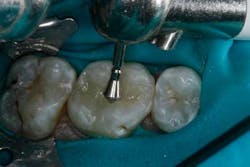

The depth of the cavity was determined to be 4 mm or less. The bulk-filled composite (Tetric EvoCeram® Bulk Fill) was placed in the preparation (Figs. 9 and 10). In this case, the first increment was placed, followed by additional material that was adapted to the tooth anatomy (Figs. 11 through 13). After further refining, the bulk-fill composite was light-cured in one increment for 10 seconds (1,200 mW/cm2).

The occlusion was checked and adjustments were completed (Figs. 14 through 16). After the final polish was accomplished, the restoration was completed (Figs. 17 through 19).